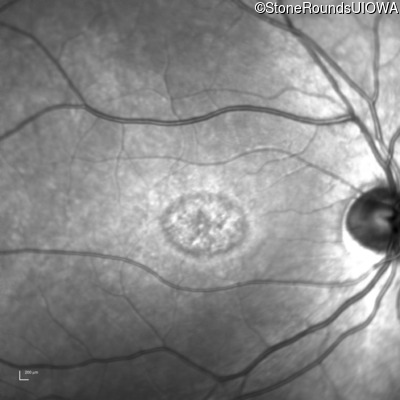

Infrared Fundus Photograph - Left - 20/50 +2

Exemplar